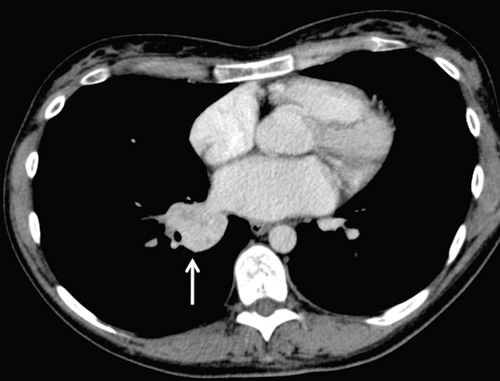

Røntgen thorax tatt omtrent et halvt år etter symptomdebut viste en litt uskarpt avgrenset fortetning i tilknytning til høyre lungehilus. Supplerende computertomografi (CT) av thorax viste en relativt velavgrenset solid fortetning, 3,7 × 3,4 × 3,5 cm, i nedre del av høyre lungehilus (fig 1). Blodprøvene viste nå normal CRP, hvite blodceller og senkningsreaksjon (SR). Pasienten hadde tørrhoste, anstrengelsesrelatert dyspné og vedvarende moderate plager i den grad at hennes fysiske yteevne var redusert. Hun hadde ingen kjent astma eller allergi. På grunn av vedvarende symptomer og røntgenfunn ble hun henvist til snarlig utredning ved lungepoliklinikken.